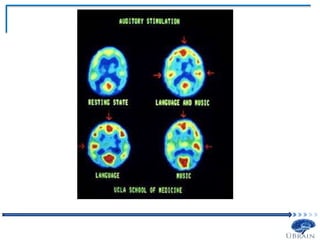

• Positron-emission tomography (PET)

 Water labelled with radioactive oxygen, is injected into a subject

 The radioactive oxygen is unstable enough that protons break off and

 These collisions are measured by a PET scanner

 It is assumed that the higher concentration of radioactive isotopes

 The more active a neuron is, the more energy it should need to

that brain region

 We use the subtraction method to determine relative levels of neural

 PET scans are taken separately for two experimental conditions

studied

difference should reflect the defining feature

C and D, the difference between the PET images for Tasks 1 and 2 should

 One consideration when using PET as an experimental technique is that it

brain

to compare too many conditions in one PET experiment